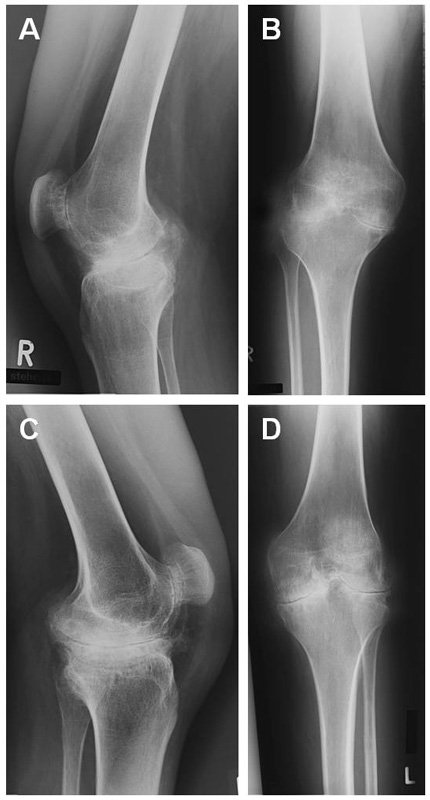

Figure 1

Preoperative x-rays of both knees. Arthrotic deformities in all three compartments of the knee joints could be observed. (a) Right knee lateral view (b) Right knee anterior-posterior view (c) Left knee lateral view (d) Left knee anterior-posterior view.

Recurrent joint haemorrhaging led to severe haemophiliac arthropathy involving knees, elbows and ankle joints. Persistent haemorrhaging and associated secondary degenerative disease led to a severe bilateral fixed knee flexion deformity of some 20° associated with severe pain and progressive difficulty in walking (fig. 1). The patient was hardly able to rise from a seated position.